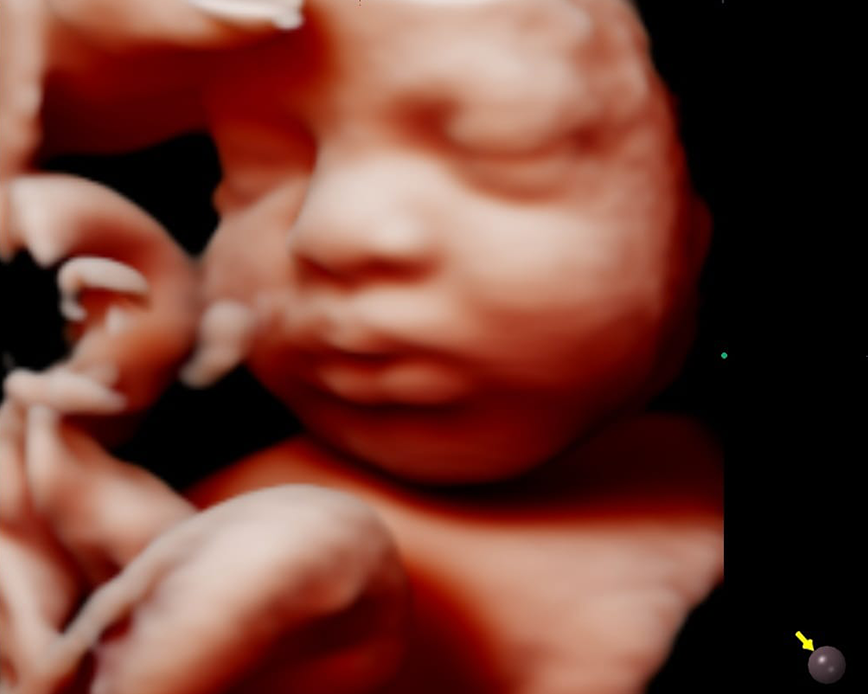

Con nuestra tecnología 5D y 6D de alta resolución, podrás ver la carita, las manos, los pies, la columna y el sexo de tu bebé con imágenes de alta calidad. Además, podrás apreciar los gestos de tu bebé en tiempo real. Esta ecografía también nos ayuda a detectar las malformaciones congénitas que pudiera tener el feto.